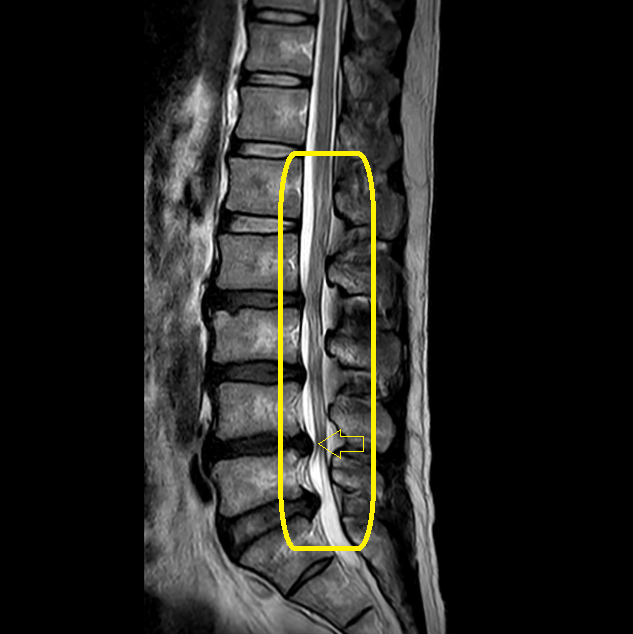

ご自身で持参されたMRI画像

(ウエストラインの左右差あり)

- ウエストラインは左が狭い:黄色矢印

脊柱管狭窄症は、身体を反ると神経の通り道が狭くなり(赤丸)足が痛くなる